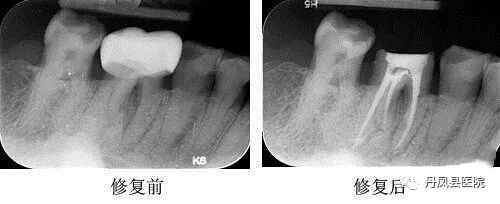

③残根保留技术:患者不拔除残根、残冠,在该基础上利用残根、残冠制作修复体,在时间上,可以缩短义齿修复的过程,是相对属于一种无创的方法。它同时还具备以下优点:

a. 残根的利用避免了拔牙及其并发症,对于年老体弱者和高血压、心脏病患者更有特殊意义。

b.保存的残根没有排斥现象,与种植义齿相比不存在排斥问题。

c. 残根的保留能够给颌骨足够的生理刺激,从而可以避免牙槽骨的吸收,有利于义齿的美观和稳固。![]()